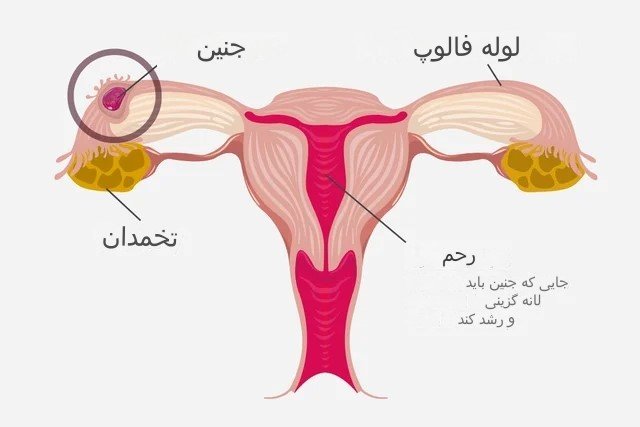

بارداری خارج از رحم چیست؟

حاملگی خارج از رحم زمانی اتفاق می افتد که تخمک بارور شده در رحم کاشته نمی شود، بلکه در جای دیگری، معمولاً در یکی از لوله های فالوپ، کاشته می شود. اگر لوله فالوپ پاره شود، خونریزی داخلی ممکن است رخ دهد. از دست دادن خون ممکن است باعث ضعف، غش، درد، شوک یا حتی مرگ شود.

گاهی اوقات خونریزی واژینال تنها علامت حاملگی خارج از رحم است. علائم دیگر ممکن است شامل درد شکم، لگن یا شانه باشد. این علائم ممکن است حتی قبل از اینکه متوجه شوید باردار هستید رخ دهد. اگر این علائم را دارید، فورا با پزشک متخصص زنان تماس بگیرید. جنین زنده نمی ماند و برای شما نیز خطر جانی دارد و باید با دارو یا جراحی برداشته شود.

حاملگی خارج از رحم: حاملگی در مکانی غیر از داخل حفره رحم، معمولاً در یکی از لوله های فالوپ.

لوله های فالوپ: لوله هایی که تخمک از طریق آنها از تخمدان به رحم می رود.